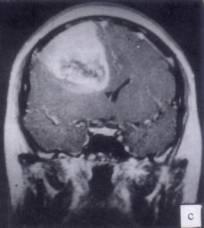

病历摘要:??患者男性,52岁。头痛伴呕吐2月,呕吐呈喷射性。既往身体健康。体检:神清,表情淡漠,反应迟钝,双眼底视神经乳头明显水肿,左鼻唇沟稍浅,左腹壁...

问题 病历摘要:??患者男性,52岁。头痛伴呕吐2月,呕吐呈喷射性。既往身体健康。体检:神清,表情淡漠,反应迟钝,双眼底视神经乳头明显水肿,左鼻唇沟稍浅,左腹壁反射减弱,左上下肢肌力4级,左Babinski征(-)。 下列的术后处理哪些是正确的?

选项 A.头高15~300卧位 B.应用止血药物 C.应用甘露醇 D.应用抗生素 E.应用糖皮质激素 F.吸氧 G.应用德巴金 H.引流管一般在术后24~48小时拔除

答案 ABCDEFGH